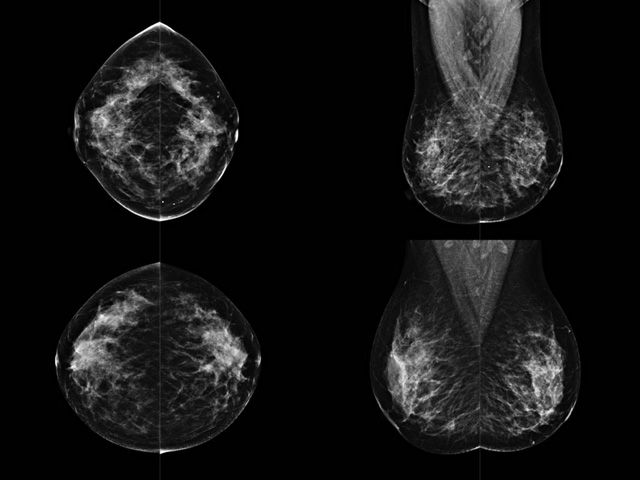

乳房檢查時候要注意一些細(xì)節(jié),需要更深入的了解這樣才能使檢查更準(zhǔn)確。乳腺DR是乳腺癌的篩查診斷工具設(shè)備。是乳房方面檢查的重要影像方法。它可以臨床檢查出早期的乳腺癌。可以判斷良性惡性。因為它可以檢查出早期的病變。對良性惡性檢查的準(zhǔn)確率達(dá)到90%以上。發(fā)病高峰年齡為45歲到54歲。50歲檢查出來乳腺癌病患,可以讓死亡率下降3成。所以30-40歲女性每年做一次乳腺DR檢查。40歲以上就一年兩次。如果家族史有乳腺癌的30歲以下也需要做檢查。清晰顯示乳腺各層組織嚴(yán)重的乳腺增生,乳腺炎,乳腺外傷也建議1年檢查一次。極大提高了早期乳腺癌的敏感度和診斷率。

大角度、高質(zhì)量的乳腺檢查,可以讓女性帶來身體健康安全。為醫(yī)生提供了高清影像數(shù)據(jù)。乳腺檢查時候各個部位影像顯示出來。白色乳腺導(dǎo)管跟纖維結(jié)締組織。模糊的是脂肪。病變一般是不透明的白色。有需要放大來檢查。乳腺DR沒有重疊偽影。輻射劑量更少。因為乳腺癌發(fā)病每年都有所提高,對女性都造成了嚴(yán)重的身體健康危害。早做檢查早治療是不可忽視的舉措。可以大大的降低死亡率。保證身體健康。一般檢查避開經(jīng)期,來完7天左右是最佳的檢查時間。絕經(jīng)的女性就沒有要求。孕婦不參加乳腺DR檢查, 6個月內(nèi)準(zhǔn)備妊娠的婦女也不宜行此檢查。